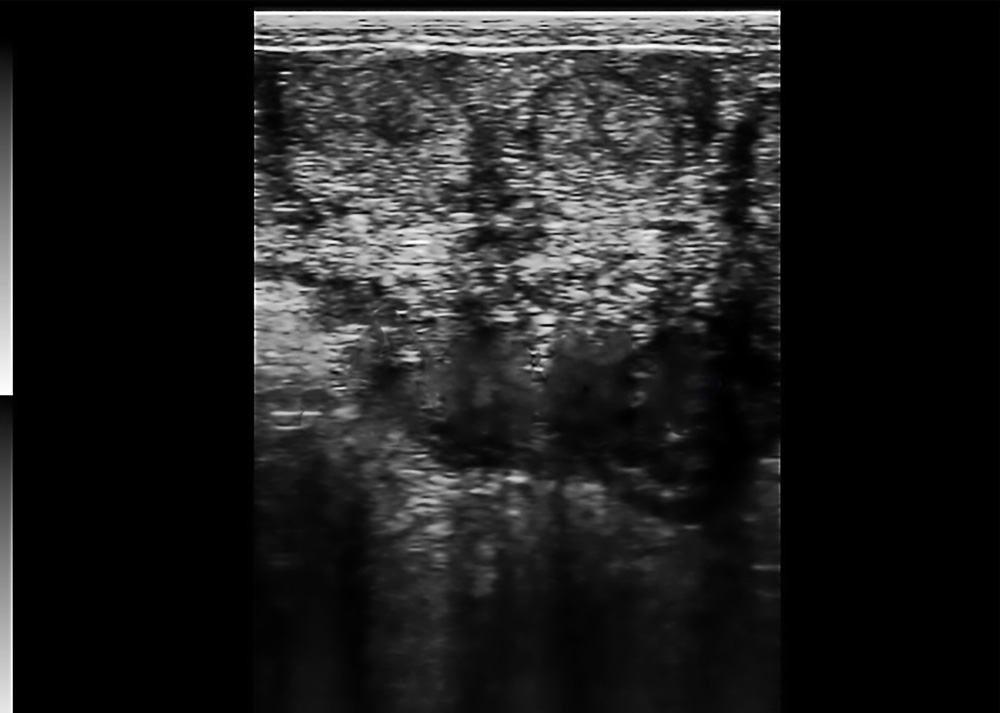

Ovarian Follicle Ultrasound

● Displays multiple follicle cavities of varied shapes.

● Layered echoes for structural recognition.

● Shows cavity distribution and size.

● For reproductive monitoring in livestock.